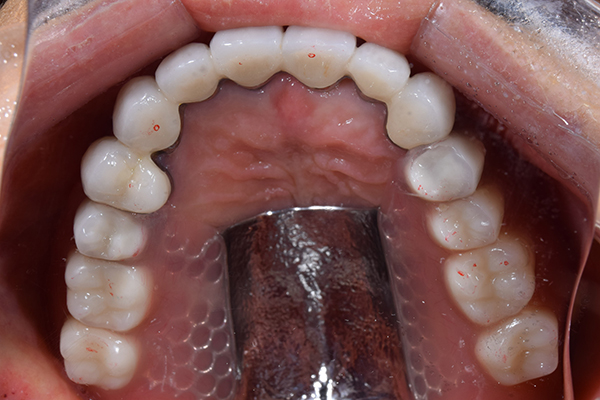

金属を使用して、薄く違和感が少ない入れ歯が完成しました。 また、見た目にも気を使い、バネが見えにくい様な構造にしました。

入れ歯をお口の中にいれた状態です。前歯もMTMといって、歯を少し引っ張り出す処置を行なったことで、しっかり残せて、またかぶせ物をしました。

義歯は下顎で、しっかり噛めること、違和感の少ないものという希望があったため、なるべく入れ歯を薄く作成するために金属をしようした義歯とした。

また、見た目もあまり義歯が目立たない様に、バネの部分を見えにくいように作成した。